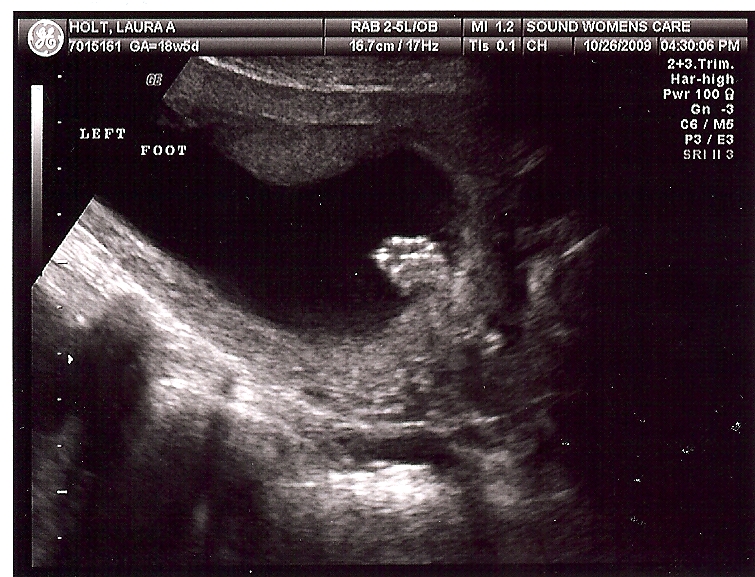

Mom. Dad. Son. Daughter. Based on our ultrasound a few days ago, we’re going to welcome a daughter into our family this March. Ethan has predicted he was going to have a sister for quite a few weeks now. She looks great and is right target for her March 24 arrival. With three nieces on both sides of our family, we should have plenty of options for clothing. We’ve included a few of the photos from our doctor’s visit.